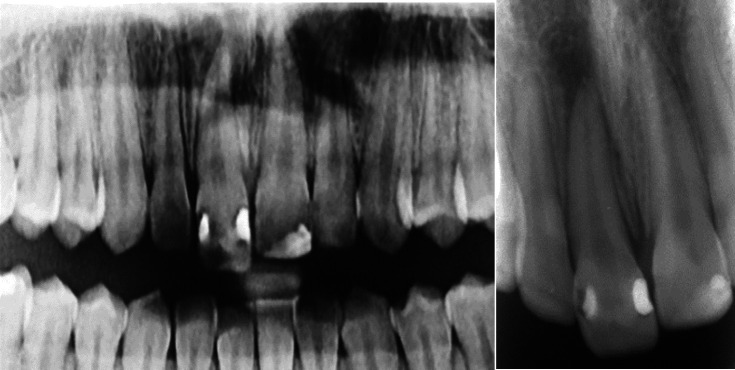

急性根尖脓肿(AAA)是一种以自发疼痛、脓形成和肿胀为特征的快速发作的炎症性疾病,通常由牙髓坏死引起。并发症可能包括全身性表现和严重的后果,如牙齿挤压。本病例报告描述了一例罕见的AAA引起上颌中切牙快速挤压的17岁女性病例。患者表现为自发的疼痛和牙齿的活动,并伴有局部肿胀。临床和影像学评估显示牙髓坏死、AAA级和根尖骨稀疏。紧急治疗开始了,包括用氢氧化钙进行管内药物治疗和暂时的牙齿夹板。随后的治疗包括用杜仲胶和密封剂进行封闭,然后进行永久性修复。5年的影像学和临床资料显示根尖周围完全愈合,牙齿活动正常,无症状复发。有效的管理,包括及时的根管治疗和夹板,导致了成功的长期结果。该病例强调了及时诊断和及时定制治疗的重要性,以管理AAA和预防严重并发症。

An acute apical abscess (AAA) is a rapid-onset inflammatory condition characterized by spontaneous pain, pus formation, and swelling, often resulting from pulp necrosis. Complications may include systemic manifestations and severe outcomes, such as tooth extrusion. This case report describes a rare instance of AAA causing rapid extrusion of a maxillary central incisor in a 17-year-old female. The patient presented with spontaneous pain and mobility of the extruded tooth, accompanied by localized swelling. Clinical and radiographic evaluations revealed pulp necrosis, an AAA, and apical bone rarefaction. Emergency treatment was initiated, including intracanal medication with calcium hydroxide and temporary splinting of the tooth. Subsequent treatment involved obturation with gutta-percha and sealer, followed by permanent restoration. Radiographic and clinical recalls up to 5 years demonstrated complete periapical healing, normal tooth mobility, and no recurrence of symptoms. Effective management, including timely root canal therapy and splinting, led to successful long-term outcomes. This case underscores the importance of prompt diagnosis and immediate, tailored treatment to manage AAA and prevent severe complications.